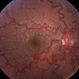

Luiz A Zago, PhD (March 17 2021)Retinal vein colateral with an active subretinal neovascular membrane. Angiogram early venous phase

By Luiz A Zago, PhD

Universidade Federal do Parana - Uploaded on Mar 14, 2021.

- Last modified by Luiz A Zago, PhD on Mar 28, 2021.

Topcon 50IX - Description

- Early phase fluorescein angiography - neovascularization with a choroid-vein anastomosis in a 25 -year -old man.